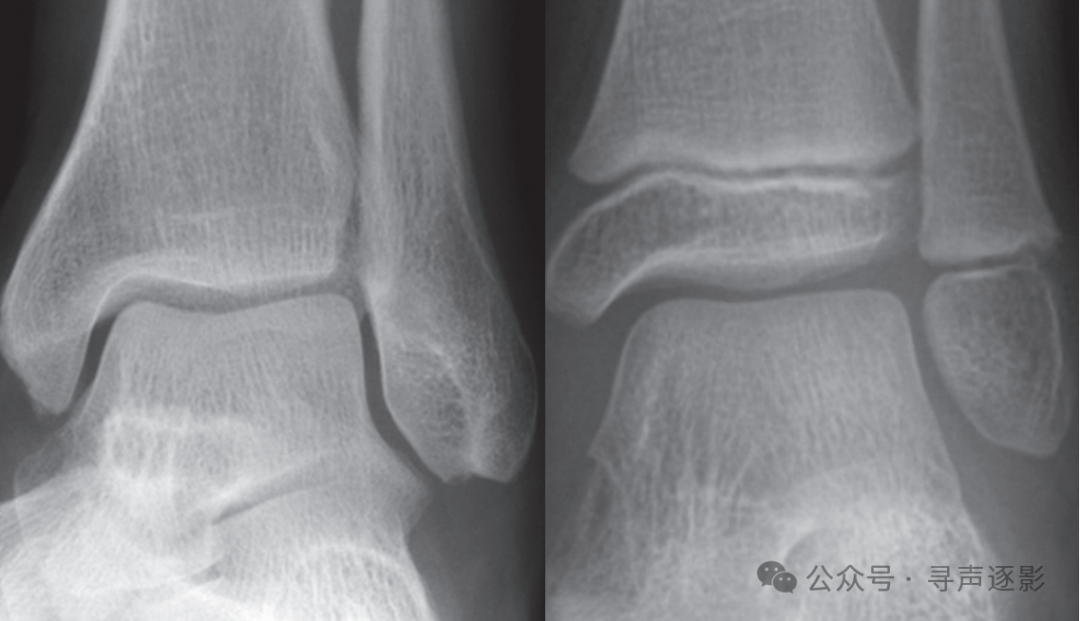

正常踝关节(左,成人;右,儿童)正位 Mortise片

【侧位】

正常踝关节侧位片